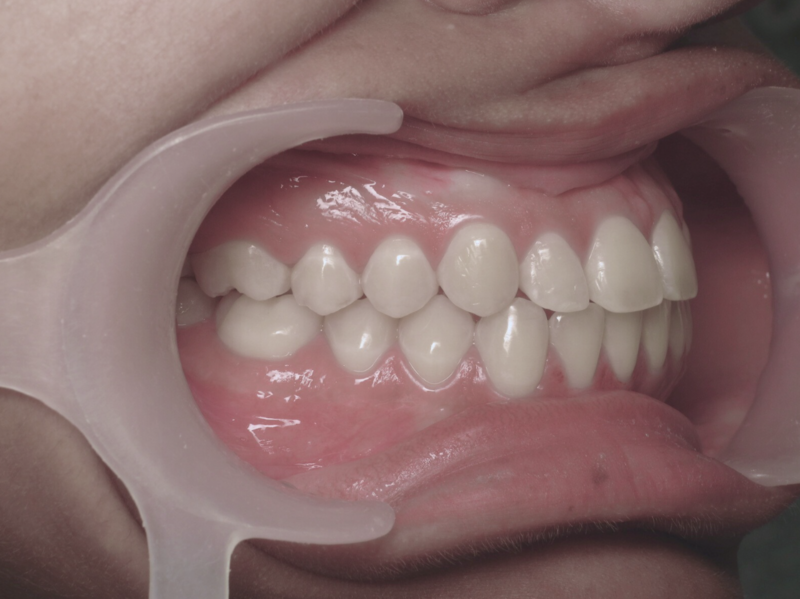

Avant

Après

Cas n°1 traité par aligneurs - adolescent

Ce cas d’une adolescente illustre la correction d'une Classe II avec supraclusion par aligneurs. La stratégie thérapeutique a reposé sur une distalisation séquentielle de l'arcade supérieure. Ce mouvement précis a permis de reculer les dents maxillaires étape par étape pour annuler le surplomb (overjet) sans extractions.

Résultats clés :

• Correction fonctionnelle : Retour à un engrènement de Classe I stable et correction du recouvrement vertical.

• Esthétique restaurée : Harmonisation globale du sourire et du profil.

• Approche moderne : Un traitement discret, confortable et hautement prévisible.

Le résultat final montre une occlusion saine et un sourire parfaitement aligné, garantissant une santé dentaire et articulaire optimale pour l'avenir.